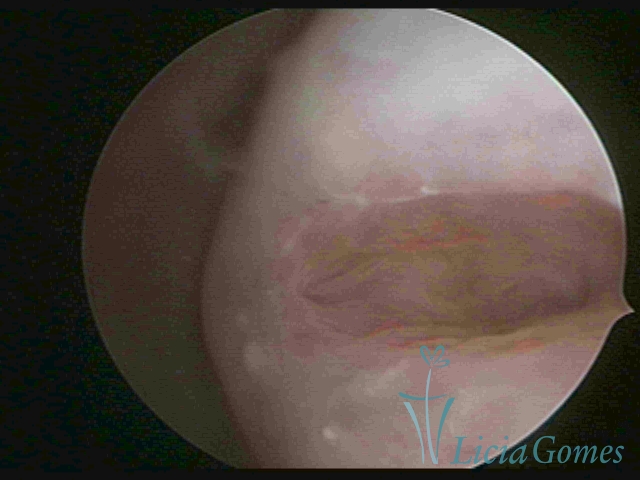

Segunda porção ou setor médio

No terço ou setor médio do canal cervical perdemos o detalhe das papilas, sendo possível a visualização de pregas e criptas. Normalmente observamos os sulcos longitudinais, que são os tecidos mais compactos, com a superfície mais vascularizada, cujos vasos seguem o seu trajeto.